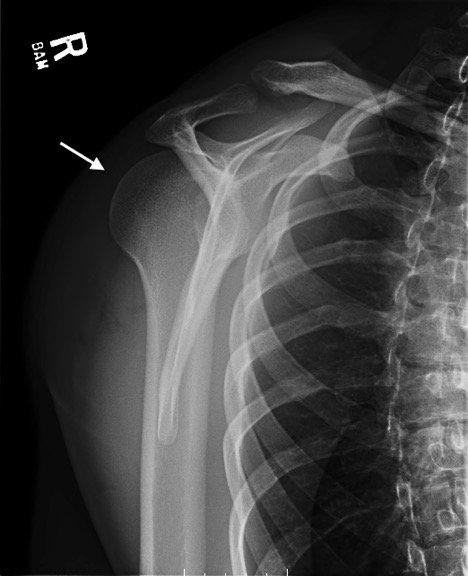

Posterior Shoulder Dislocation, Y View XR, Annotated. JETem 2017

Irreducible Traumatic Posterior Shoulder Dislocation